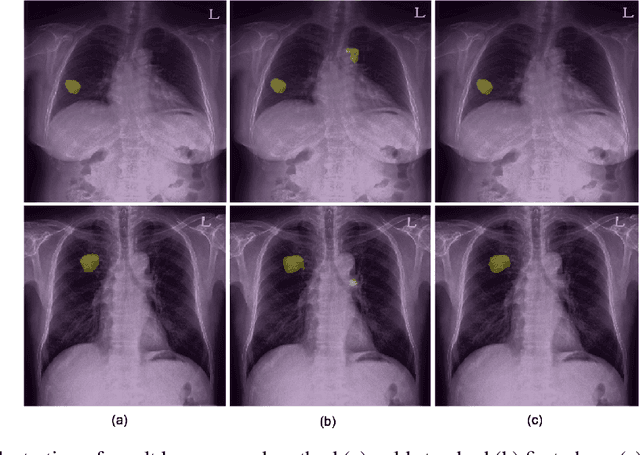

Abstract:Machine learning applications in medical imaging are frequently limited by the lack of quality labeled data. In this paper, we explore the self training method, a form of semi-supervised learning, to address the labeling burden. By integrating reinforcement learning, we were able to expand the application of self training to complex segmentation networks without any further human annotation. The proposed approach, reinforced self training (ReST), fine tunes a semantic segmentation networks by introducing a policy network that learns to generate pseudolabels. We incorporate an expert demonstration network, based on inverse reinforcement learning, to enhance clinical validity and convergence of the policy network. The model was tested on a pulmonary nodule segmentation task in chest X-rays and achieved the performance of a standard U-Net while using only 50% of the labeled data, by exploiting unlabeled data. When the same number of labeled data was used, a moderate to significant cross validation accuracy improvement was achieved depending on the absolute number of labels used.

Abstract:Generating large quantities of quality labeled data in medical imaging is very time consuming and expensive. The performance of supervised algorithms for various tasks on imaging has improved drastically over the years, however the availability of data to train these algorithms have become one of the main bottlenecks for implementation. To address this, we propose a semi-supervised learning method where pseudo-negative labels from unlabeled data are used to further refine the performance of a pulmonary nodule detection network in chest radiographs. After training with the proposed network, the false positive rate was reduced to 0.1266 from 0.4864 while maintaining sensitivity at 0.89.